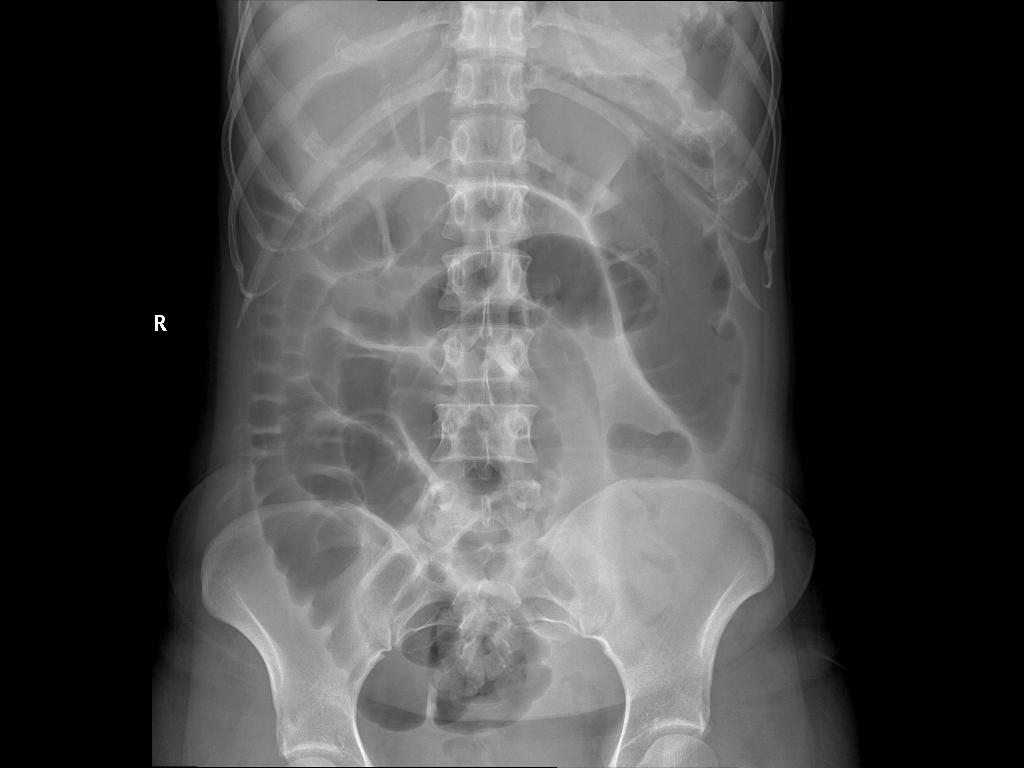

在外科的门诊,接到了这样的一个患者,该患者四天的时间,吃了二三十斤的橘子,并且他吃橘子没有吐核的习惯,因为肚子疼痛难忍,最后住院了,住院之后就开始查病因,先是我们外科大夫进行触诊检查,能够明显的摸到该患者的腹部有硬的团块,拍来片子一看,大家都震惊了,一团被压的实实东西死死地堵在了肠管内,形成了食源性肠梗阻,而这一团导致肠梗阻的东西,就是该患者吃的橘子核。